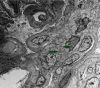

Immunoglobulin A (IgA)-dominant infection-related glomerulonephritis (IRGN) is mostly associated with Staphylococcal or other bacterial infections like Streptococcus and Gram-negative bacilli. Antibiotics are the cornerstone of treatment in these cases. When the bacterial infection can't be recognized or IRGN persists despite treating the underlying infection, controlling the kidney injury becomes cumbersome and lacks a strong evidence-based approach. In this report, we describe a 38-year-old male patient with a history of polysubstance abuse and chronic hepatitis B and hepatitis C infections who presented with acute kidney injury and nephrotic syndrome due to IgA-dominant IRGN without an active concurrent bacterial infection who responded well to plasmapheresis.